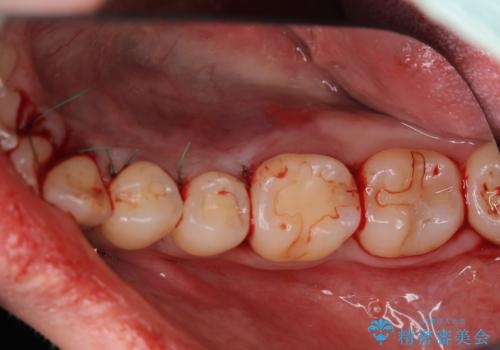

- 下顎の骨隆起を取りたいとのことで来院された患者様です。

一般的な歯科治療で用いる局所麻酔下で進めていきます。

右側と左側で2回に分けて行いました。

術後1週間での抜糸となります。